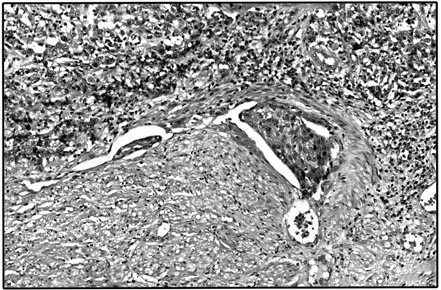

Tumor embolus present within vascular space.